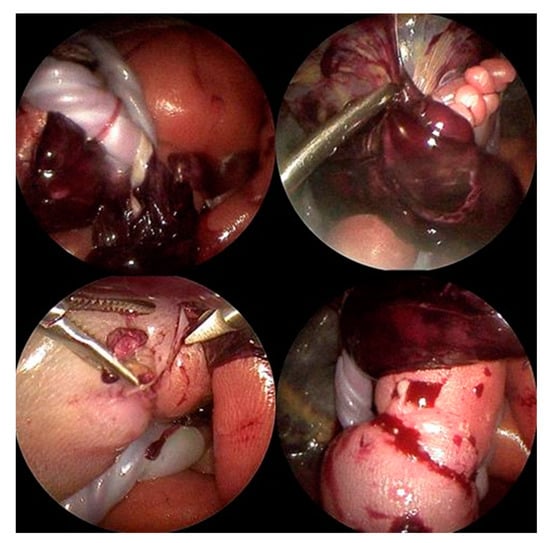

As already suspected in the ultrasound examination, the fetus was seen to lie in a blood-tainted amniotic cavity covered by amniotic material (Figure 3). As the left foot was protruding through a hole in the abrupted placenta, the fetus might have torn it off with a wrong movement, which, in the worst case, could have resulted in severe maternal hemorrhage. The umbilical cord was surrounded by multiple strings of the detached amniotic sac, and the proximal right calf was constricted by a tight, circumferential amniotic band (Figure 4).

Visualized by a 3.3 mm 30-degree rod-lens fetoscope, all amniotic bands, as well as the abrupted placental segment, were dissected using endoscopic scissors and graspers (Figure 4). Following dissection of the band that strangulated the proximal right calf, the extremity distal to the constriction quickly turned pink again, heralding promise for its preservation.

Subsequently, all strands of amniotic material that were twisting and entangling the umbilical cord were also dissected. After successful removal of all bands from both the fetus and its surroundings, to prevent new attachments, the insufflation was halted and the amniotic cavity was refilled with warmed, sterile crystalline solution. Following trocar removal, the maternal abdominal skin incisions were closed with single sutures.

As the left foot of the fetus was stuck within the detached part of the placenta (Figure 4), the fetus could have fully abrupted the placenta with a wrong movement, which, in the worst case, would have resulted in severe hemorrhage for the mother. Therefore, the aim of this surgery was not only to improve the chance of fetal survival but also to mitigate the dangerous situation for the mother by pulling the left fetal foot out of the placenta completely. As all potential complications attributable to the procedure could have occurred during the natural, untreated disease course, there was justification to perform the operation in view of saving the fetal life.

Figure 4. Top left: Multiple annular amniotic bands were entangling the umbilical cord and placental tissues. Top right: The fetal left foot was stuck within a part of the placenta, both restricting fetal movement and placing the mother and fetus at high risk of hemorrhage. Bottom left: A tight amniotic band encircling the right fetal calf caused severe strangulation, which would have led to partial limb autoamputation if left unresolved. Bottom right: After dissection of the right leg constriction due to the amniotic band, blood flow to the calf and foot improved immediately.